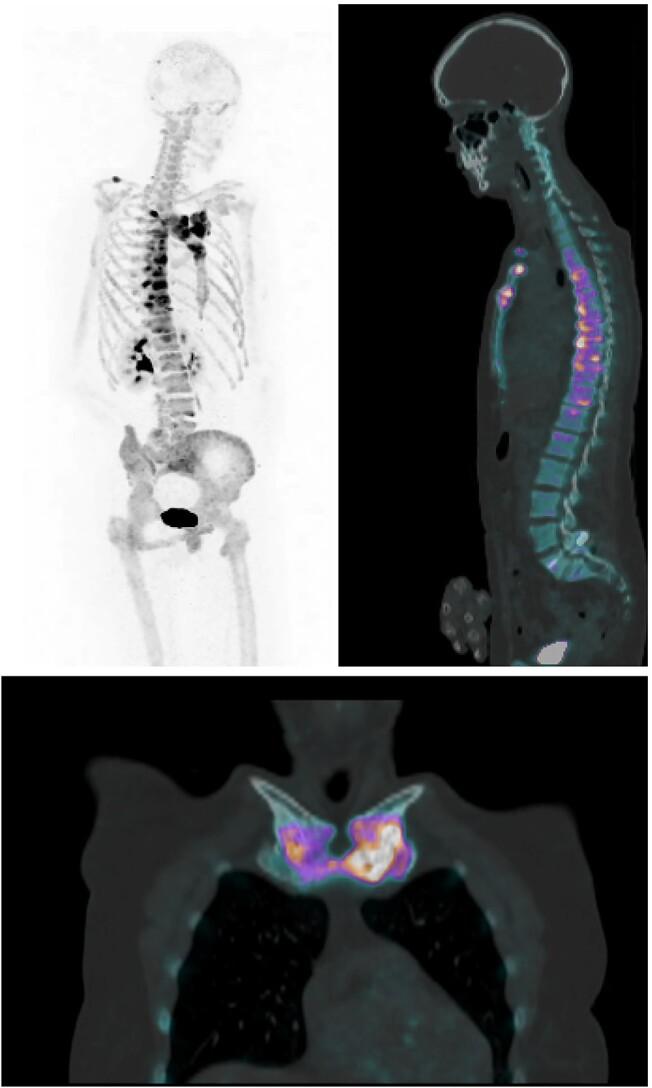

Chronic nonbacterial osteitis (CNO) is a rare disease spectrum, which lacks biomarkers for disease activity. Sodium fluoride-18 positron emission tomography/computed tomography ([F]NaF-PET/CT) is a sensitive imaging tool for bone diseases and yields quantitative data on bone turnover. We evaluated the capacities of [F]NaF-PET/CT to provide structural and functional assessment in adult CNO. A coss-sectional study was performed including 43 adult patients with CNO and 16 controls (patients referred for suspected, but not diagnosed with CNO) who underwent [F]NaF-PET/CT at our expert clinic. Structural features were compared between patients and controls, and maximal standardized uptake values (SUV [g/mL]) were calculated for bone lesions, soft tissue/joint lesions, and reference bone. SUV was correlated with clinical disease activity in patients. Structural assessment revealed manubrial and costal sclerosis/hyperostosis and calcification of the costoclavicular ligament as typical features associated with CNO. SUV of CNO lesions was higher compared with in-patient reference bone (mean paired difference: 11.4; 95% CI: 9.4-13.5; p < .001) and controls (mean difference: 12.4; 95%CI: 9.1-15.8; p < .001). The highest SUV values were found in soft tissue and joint areas such as the costoclavicular ligament and manubriosternal joint, and these correlated with erythrocyte sedimentation rate in patients (correlation coefficient: 0.546; p < .002). Our data suggest that [F]NaF-PET/CT is a promising imaging tool for adult CNO, allowing for detailed structural evaluation of its typical bone, soft-tissue, and joint features. At the same time, [F]NaF-PET/CT yields quantitative bone remodeling data that represent the pathologically increased bone turnover and the process of new bone formation. Further studies should investigate the application of quantified [18F]NaF uptake as a novel biomarker for disease activity in CNO, and its utility to steer clinical decision making.

慢性非细菌性骨炎(CNO)是一种罕见的疾病谱,缺乏疾病活动的生物标志物。18氟氟化钠正电子发射断层扫描/计算机断层扫描([F]NaF-PET/CT)是一种用于骨疾病的敏感成像工具,可提供骨转换的定量数据。我们评估了[F]NaF-PET/CT在成人CNO中进行结构和功能评估的能力。进行了一项横断面研究,纳入了43例成年CNO患者和16例对照(因疑似但未确诊CNO而转诊的患者),他们在我们的专家门诊接受了[F]NaF-PET/CT检查。比较了患者和对照之间的结构特征,并计算了骨病变、软组织/关节病变和参考骨的最大标准化摄取值(SUV[g/mL])。SUV与患者的临床疾病活动相关。结构评估显示,胸骨柄和肋骨硬化/骨质增生以及肋锁韧带钙化是与CNO相关的典型特征。与住院患者参考骨相比,CNO病变的SUV更高(平均配对差异:11.4;95%CI:9.4-13.5;p < .001),与对照相比也更高(平均差异:12.4;95%CI:9.1-15.8;p < .001)。最高的SUV值出现在软组织和关节区域,如肋锁韧带和胸骨柄关节,这些与患者的红细胞沉降率相关(相关系数:0.546;p < .002)。我们的数据表明,[F]NaF-PET/CT是一种用于成人CNO的有前景的成像工具,能够对其典型的骨、软组织和关节特征进行详细的结构评估。同时,[F]NaF-PET/CT产生的定量骨重塑数据代表了病理性增加的骨转换和新骨形成过程。进一步的研究应调查定量[18F]NaF摄取作为CNO疾病活动的新型生物标志物的应用,以及其指导临床决策的效用。